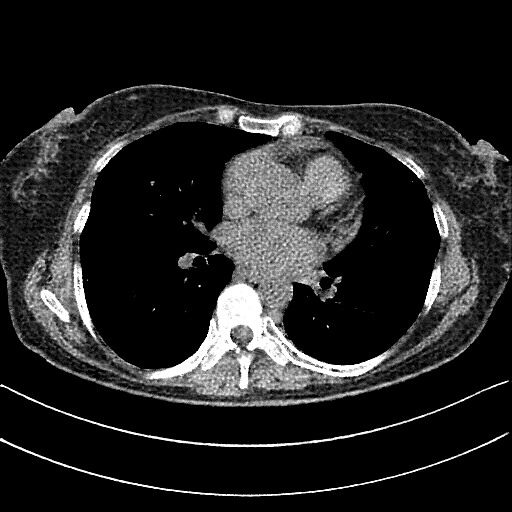

Original VENOUS CT scan

No window - Raw intensity values

Original VENOUS CT scan

Lung window (WL -600, WW 1500 → Low −1350, High +150)

Original VENOUS CT scan

Mediastinum window (WL 40, WW 400 → Low −160, High +240)

Generated VENOUS CT scan (A→B translation)

No window - Raw intensity values

Generated VENOUS CT scan (A→B translation)

Lung window (WL -600, WW 1500 → Low −1350, High +150)

Generated VENOUS CT scan (A→B translation)

Mediastinum window (WL 40, WW 400 → Low −160, High +240)